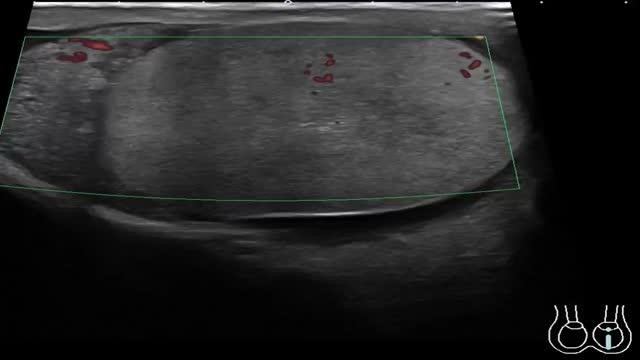

Rotación del testículo sobre sí mismo de forma que el cordón espermático con los vasos testiculares se torsiona y se produce un compromiso vascular. Es una urgencia quirúrgica por el riesgo de isquemia del testículo si no se interviene en las primeras 4-6h.

La ecografía es poco específica en el modo B, cuando se detectan alteraciones en la ecogenicidad es en los casos de torsión avanzada, en los que puede haber una ecogenicidad heterogénea con áreas hipoecogénicas debido a la congestión, edema e infarto, así como un claro aumento de tamaño del testículo afectado. Es imprescindible utilizar el modo Doppler para el diagnóstico. Inicialmente existe una ausencia de flujo venoso y posteriormente también arterial en el testículo afecto al compararlo con el contralateral (Fig. 8). Ha de confirmarse la presencia de flujo en las venas y en las arterias intratesticulares mediante la técnica Doppler espectral (pulsado). Respecto al cordón espermático se puede visualizar el giro o tirabuzón del cordón, conocido como «whirlpool sign». Es muy específico de torsión testicular y se manifiesta como una masa con forma de espiral de localización posterosuperior al testículo con ausencia de flujo o escaso flujo en los casos de torsión intermitente (vídeo 4). En los casos de resolución espontánea se puede ver un flujo intratesticular muy aumentado debido a la llamada fase de reperfusión1,9,28,30.